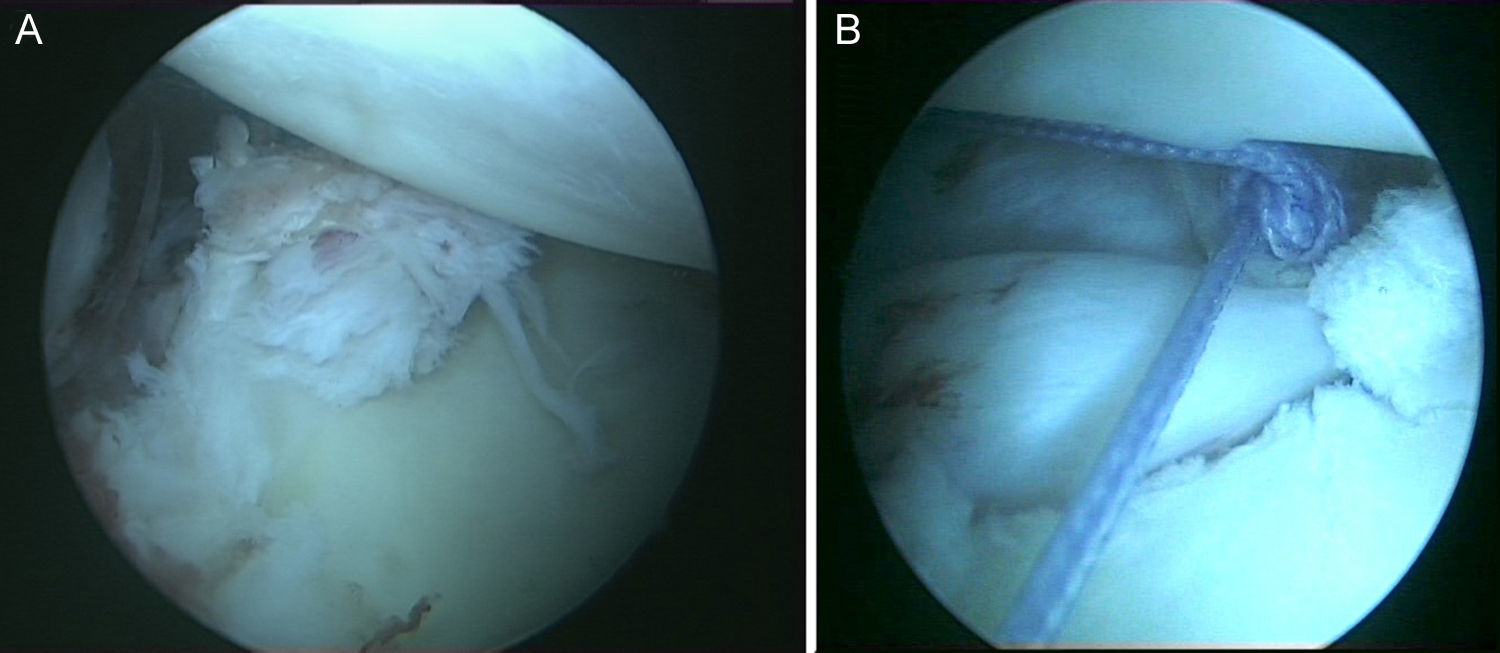

Técnica quirúrgicaBajo anestesia general y locorregional (bloqueo interescalénico), se intenta reducir el hombro de forma cerrada. En caso de no conseguirlo se coloca al paciente en decúbito lateral con tracción de unos 5kg y, siguiendo la técnica descrita por Verma5, se introduce un «Wissinger» por el portal posterior estándar, el que empleamos para la artroscopia de hombro. Con el «Wissinger» a través del portal realizamos tracción de la cabeza humeral hacia lateral, apoyándonos en la cápsula y en la parte posterior del manguito, no en el hueso. Habitualmente con esta maniobra conseguimos introducir la cabeza humeral en la glenoides y podemos pasar a realizar la artroscopia de hombro. En caso de no conseguir una reducción, pasaríamos a realizar una reducción abierta con el paciente en posición de silla de playa y con una vía de abordaje anterior al hombro. Con el hombro reducido se realiza la artroscopia de hombro. Se emplean los portales posterior, anterosuperolateral, anterior, portal de Wilmington y portal posteroinferior. Se estudia la lesión de Hill-Sachs inverso, la relación con el tendón del subescapular y la lesión del labrum posterior (fig. 2, figs. 3 y 4), el resto del labrum y el manguito de los rotadores. Hay que limpiar bien la articulación, extirpar todo el tejido fibroso, liberar el labrum posterior de las adherencias a la glena, preparar el lecho óseo de la glena antes de colocar los implantes (en el caso 1 se emplearon 2 implantes Lupine BR [DePuy Mitek, Raynham, MA], y el caso 2 con un Gryphon BR [DePuy Mitek, Raynham, MA] cargado con doble sutura), realizar la reconstrucción capsulolabral con un pasador directo o indirecto, anudar y cortar las suturas. Una vez reparadas las lesiones soltamos el brazo del sistema de tracción y comprobamos la relación de la cabeza humeral, del defecto óseo anterior con la glenoides, al hacer rotaciones del hombro (sobre todo si hay riesgo de «enganche» con la rotación interna), y decidimos si fijamos el tendón del subescapular en el defecto óseo humeral anterior, tal y como describió Krackhardt6.

No es estrictamente necesario que reproduzcamos un enganche de la lesión de Hill-Sachs inversa para decidir realizar el remplissage inverso. Con la óptica en el portal anterosuperolateral liberamos el tendón del subescapular, su cara anterior y posterior. Preparamos el lecho óseo de la cabeza humeral, extirpando todo el tejido fibroso de la lesión de Hill-Sachs inversa, con el sinoviotomo, la fresa de hueso o periostotomos, hasta obtener hueso sangrante. Entonces desde el portal anterior, insertamos los implante en el defecto óseo (en el caso 1 un 5,5 Healix BR [DePuy Mitek, Raynham, MA] con 2 suturas UHMWPE [Orthocord; DePuy Mitek]) en el tercio superior y en la zona más medial del defecto (fig. 5), y en el caso 2 insertamos 2 Gryphon BR Healix BR (DePuy Mitek, Raynham, MA) con 2 suturas UHMWPE (Orthocord; DePuy Mitek), uno inferior y otro superior en la zona más medial del defecto óseo. Recuperaremos las suturas desde un portal anterosuperior accesorio y con una pinza para atravesar el tendón (Penetratror DePuy Mitek, Raynham, MA) a través del portal anterior, atravesamos el tendón del subescapular y recuperamos las suturas. Daremos puntos colchoneros, uno inferior y otro superior, para conseguir un buen contacto del tendón con el hueso, separando los puntos entre 1 y 2cm (fig. 6). Podemos ayudarnos con un empujanudos a través del portal anterosuperior accesorio para el manejo y recuperación de las suturas, acercándolas a la boca de la pinza penetrator, tratando de no mover en exceso la pinza una vez atravesado el tendón, para evitar lesionar el tendón y el cartílago. Manteniendo el brazo en 35-40° de rotación interna anudamos primero el punto inferior y luego el superior (figs. 7 y 8).

Caso 1, hombro derecho. A. Vista desde el portal ASL de la lesión de Hill-Sachs inversa con el implante en el tercio medial del defecto óseo. B. Imagen después de hacer los nudos; podemos ver el tendón del subescapular rellenando parcialmente el defecto óseo de la cabeza humeral, con la cabeza centrada en la cavidad.